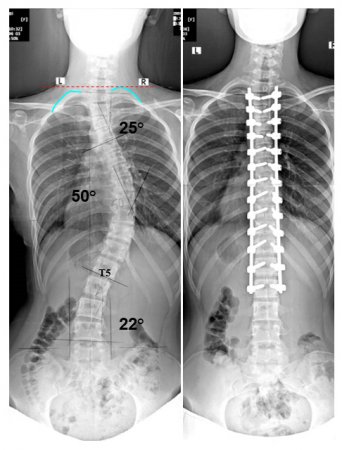

Omurga operasyonlarında gelişebilecek sorunlar

Omurga operasyonları zor ve tecrübe gerektiren operasyonlardır. Omurga operasyonları riskli ameliyatlardır. Bu riskler yapılacak omurga

sorununa ve genişliğine göre farklılıklar göstermektedir. Yapılacak omurga segment sayısı arttıkça çıkabilecek sorunlar artmaktadır.

Skolyoz ve kifoz cerrahisinde riskler daha fazla ve çıkabilecek komplikasyonlar çok daha fazladır.Bu gelişebilecek erken veya geç

Omurgada kaymalar olabilir, omurgada kırıklar olabilir, omurgada eğrilikler kifoz veya skolyoz olabilir. İşte bu sorunlar derecelerine tespit